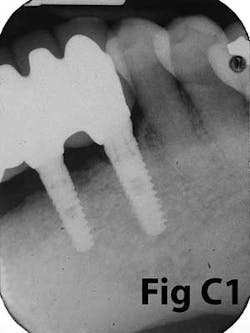

There is an abundance of literature showing increased gingival inflammation around natural dentition (exacerbated when a fixed restoration is present) when there is less than 2 mm AG. (Figs. 8, 9: post grafting) There is an abundance of literature showing increased incidence of peri-implant mucositis when there is inadequate attached tissue — a weaker connective tissue adhesion and lack of Sharpey’s fibers make the peri-implant tissue even more susceptible to bacterial challenge. (1-6, 8, 10) And as periodontitis is always preceded by gingivitis, peri-implantitis will be preceded by peri-implant mucositis. If we can decrease the incidence of peri-implant mucositis by providing a better and more resilient tissue phenotype, we can lower the incidence of peri-implantitis.The FGG procedure is indicated in cases of implant therapy where this is less than 2 mm of attached tissue present. Sometimes, a FGG is preferred over CTG because: (1) the FGG results in greater gain of attached tissue, (2) the FGG alleviates frenum/muscular pull whereas the connective tissue may increase muscular tension after the flap is coronally advanced, and (3) creeping attachment is often a positive byproduct of the FGG procedure.

Refer to Case Nos. 1 & 2.

Case No. 1

Case No. 2